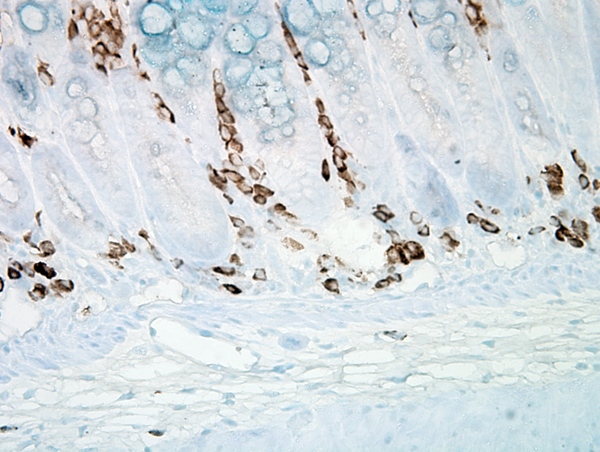

IHC (Immunohistochemistry)

(Immunohistochemistry analysis using Mouse Anti-Nitrotyrosine Monoclonal Antibody, Clone 39B6. Tissue: colon carcinoma. Species: Human. Fixation: Formalin. Primary Antibody: Mouse Anti-Nitrotyrosine Monoclonal Antibody at 1:25000 for 12 hours at 4 degree C. Secondary Antibody: Biotin Goat Anti-Mouse at 1:2000 for 1 hour at RT. Counterstain: Mayer Hematoxylin (purple/blue) nuclear stain at 200 ul for 2 minutes at RT. Magnification: 40x.)